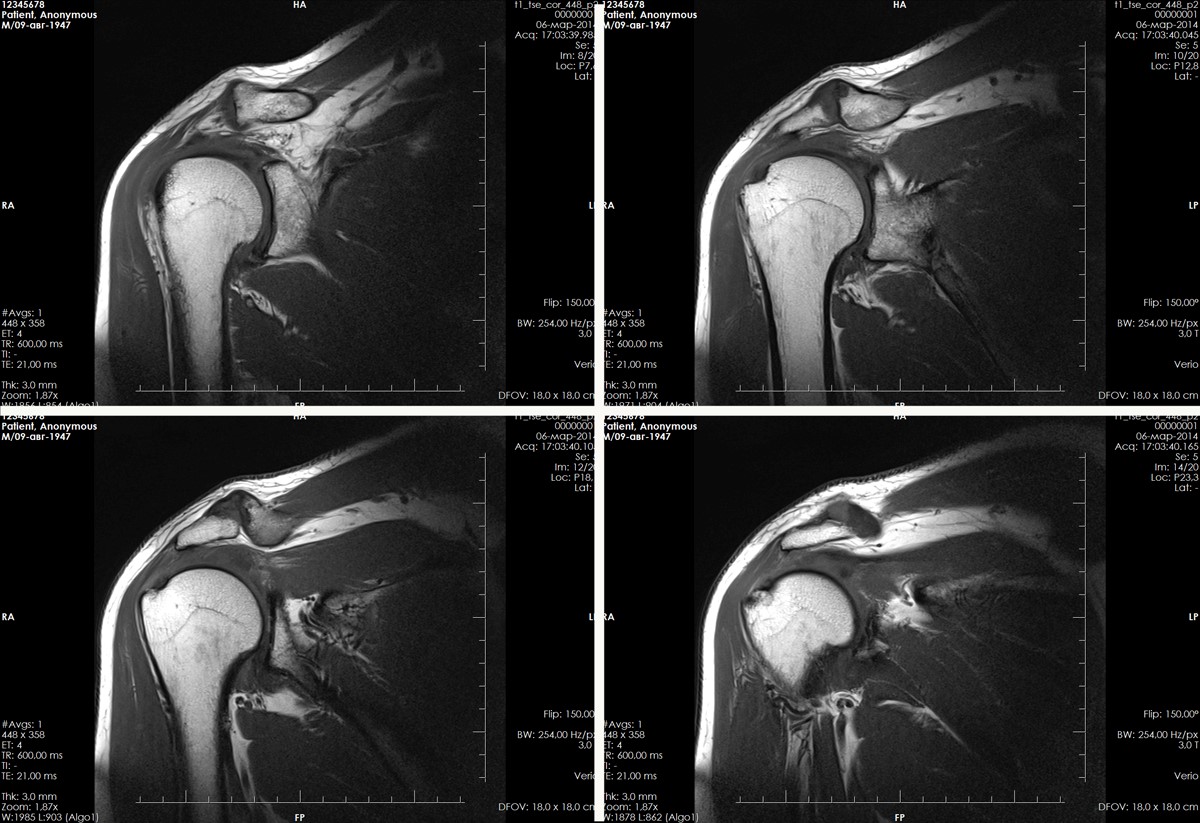

Вывих плеча — одна из наиболее распространенных травм верхних конечностей. Он может быть первичным (свежим) или привычным. Магнитно-резонансная томография помогает выявить повреждения в суставе и связочном аппарате при обоих типах вывиха.

Первичный вывих плеча на МРТ

Первичный вывих плеча — это травма, возникающая при механическом воздействии на сустав, часто из-за интенсивных физических нагрузок. Такой вывих называют свежим. МРТ плечевого сустава позволяет визуализировать структуру, соединяющую плечевую кость с ключицей и лопаткой, а также окружающие ткани. На снимках МРТ видны связки, мышцы, сухожилия, сосуды и нервы.

Привычный вывих плеча на МРТ

Привычный вывих плеча — это следствие патологических процессов в связочном аппарате сустава. Даже минимальная травма или обычные действия могут вызвать его. Обследование помогает определить степень разрыва капсулы сустава, связок и мышц, а также уточнить результаты рентгенографии и КТ, которые выявляют повреждения костей наряду с МРТ. Признаки привычного вывиха плеча включают травму сухожилий и подлопаточной мышцы, разрыв суставной губы и синовит. МРТ также необходимо для диагностики сдавливания сосудов и нервов плеча.